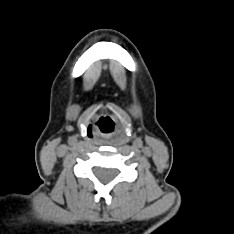

Что может выявить КТ щитовидной железы

- узловые образования и их положение относительно трахеи, пищевода, сосудистых пучков;

- злокачественные и доброкачественные опухоли;

- увеличение размеров органа;

- поликистоз;

- состояния, связанные с избыточным продуцированием гормонов щитовидной железы.

- воспалительные процессы;

- атрофию и гипоплазию (врожденное уменьшение железы или недоразвитие ее отдельной части);

- нарушение кровообращения (артериальную и венозную гиперемию);

- кровоизлияния в ткани органа и многое другое.